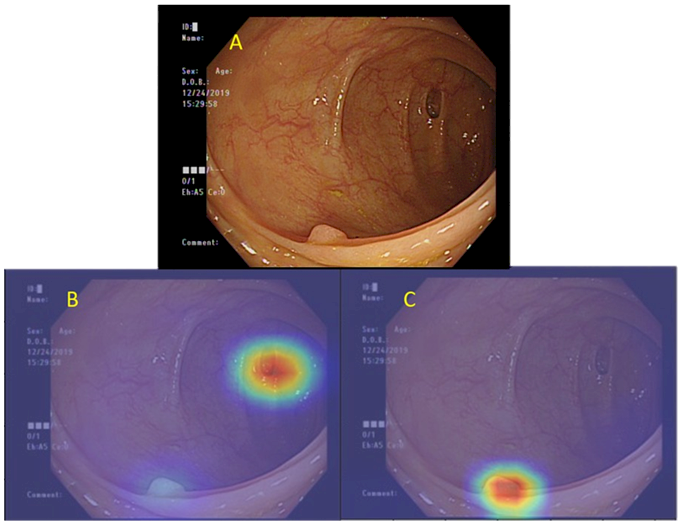

▲ 當多重大腸病灶同時出現在一張影像上(A),人工智慧系統也能準確診斷(B)為憩室、(C)為大腸瘜肉。(Source:北榮)

台北榮總內視鏡團隊研發出「腸道內視鏡多模態輔助診斷系統」,可同時辨識瘜肉、憩室、盲腸,協助醫師判別大腸鏡檢查是否已到達最後最深的位置,及大腸癌等多種病灶,平均準確度達 90% 以上。此外,更可進一步判斷瘜肉是否為可能轉變為惡性的的腺瘤性瘜肉。